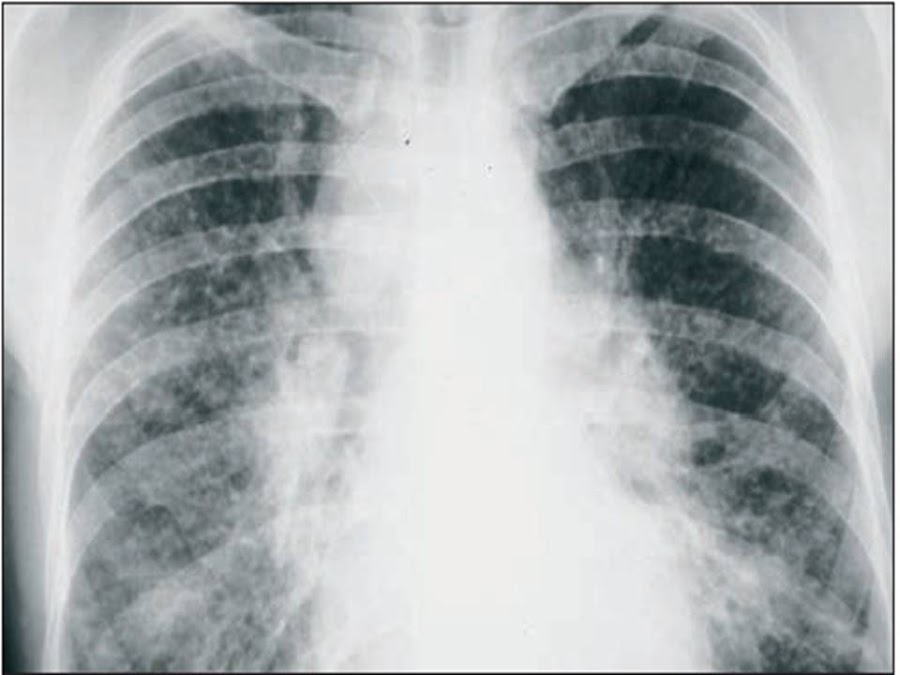

Los infiltrados suelen estar en campos medios y superiores (Figura 3). Predomina el patrón retículonodular, pero también se observan infiltrados alveolares, consolidación o masas. La tomografía axial computadorizada (TAC) es más sensible para detectar adenopatías, a veces calcificadas en forma de cristal esmerilado y lesiones parenquimatosas. La sarcoidosis pulmonar puede evolucionar a fibrosis pulmonar y desarrollo de hipertensión pulmonar secundaria, sin embargo, no siempre hay una relación entre los cambios radiográficos y el compromiso funcional respiratorio, por lo que deberán asociarse a la radiología simple otros métodos de evaluación, tales como la TAC de alta resolución, el lavado bronco-alveolar, la gammagrafía con Galio, estudios de capacidad ventilatoria y, si fuese necesario, la biopsia pulmonar.

Figura 3.- Adenopatías hiliares bilaterales y paratraqueal derecha con infiltrado pulmonar reticulonodulillar bilateral de predominio en campos medios y superiores.